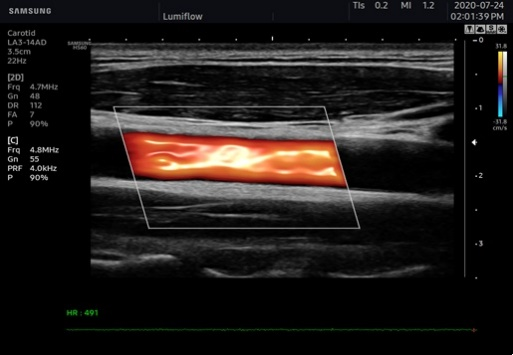

LumiFlowTM 立体血流成像

三星彩超怎么样AI辅助,更精准、更清晰!淮安三院引进两台三星XR7高档彩超_https://www.jmylbn.com_新闻资讯_第3张

LumiFlowTM 是一种立体血流成像,通过血流的三维可视化,有助于直观地了解血流、小血管的结构走形、与周围组织的关系。可与彩色多普勒、能量图、S-flow、MV-flow等联合使用。